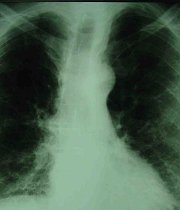

Los científicos identificaron una variación genética común que aparece vinculada con un riesgo sustancialmente mayor de fibrosis pulmonar, según un artículo que publicó la revista New England Journal of Medicine.

ImagenLos Institutos Nacionales de Salud, conocidos por su sigla en inglés NIH y que financiaron el estudio, indicaron que la variación genética se encuentra en una región del ácido desoxirribonucleico que, según se cree, regula la producción de una proteína importante en la formación de mucosidad.

La enfermedad, causada por la cicatrización o engrosamiento de los pulmones sin una causa conocida, afecta posiblemente a unas 100.000 personas en Estados Unidos y a unos cinco millones en todo el mundo.

Esta enfermedad hace que los pulmones se cicatricen y se tornen rígidos, lo que hace que cada vez sea más difícil respirar.